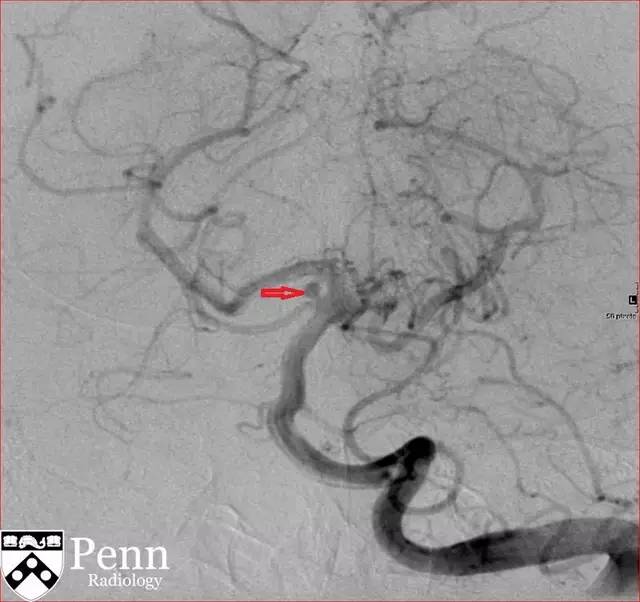

图 4 DSA 可见囊样动脉瘤(红色箭头)

图 7 动脉瘤栓塞术后 DSA,可见动脉瘤内无对比剂充盈(红色箭头)

图 8 动脉瘤栓塞术后 DSA,可见动脉瘤内无对比剂充盈(红色箭头)

DSA:是诊断血管病变的金标准,具有非常高的空间分辨率和时间分辨率。可在动脉分叉处看到囊状影。破裂部位常可看到「墨菲乳头」。